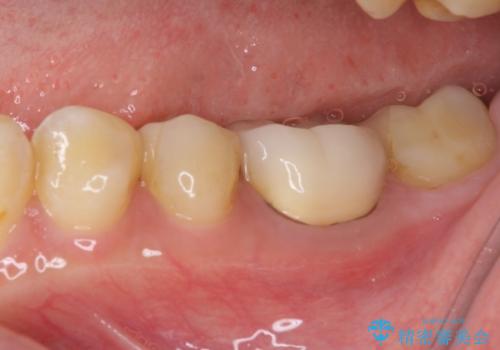

精密に型取りを行ったセラミックインレーを装着したことで、治療後にはしみたり痛んだりという症状は治まりました。